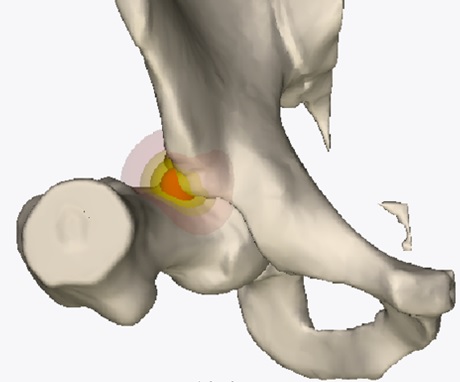

La diagnosi differenziale più frequente in ambito sportivo e nell’ottica della Groin Pain Syndrome è quella del conflitto femoro-acetabolare (FAI, Femoral Acetabular Impingement). Il paziente lamenta un dolore profondo difficilmente localizzabile in corrispondenza dell’anca o della regione inguinale. Solitamente insorge dopo uno sforzo, non sempre correlato a un trauma. Affligge il paziente per lungo tempo e si riesacerba in particolare con l’attività fisica. Può verificarsi una progressiva limitazione dell’articolarità dell’anca e durante la mobilizzazione si possono avvertire “click” e rumori articolari, anche dolorosi. Può concomitare cedimento dell’arto inferiore o sensazione di sublussazione. Le maggiori limitazioni in ambito sportivo sono i movimenti tipo “squat”, gli affondi, i cambi di direzione, le torsioni e le decelerazioni. I sintomi possono divenire invalidanti rendendo disagevole anche la posizione durante la guida della propria auto, lo stare seduti in ufficio, la deambulazione e il riposo notturno sul fianco affetto.

L’equipe della Chirurgia Ortopedica Ricostruttiva Tecniche Innovative ha messo a punto un percorso diagnostico-terapeutico dedicato ai pazienti affetti da coxalgia. L’iter prevede visita specialistica e l’integrazione con esami strumentali mirati (ecografia dinamica (fig. 5), radiografie con proiezioni specifiche, ricostruzioni tridimensionali TC (fig. 6), RMN ad alto campo, test con anestetico intra o extra-articolare).